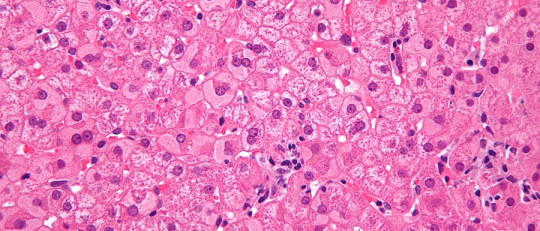

Las meninges son un conjunto de capas protectoras situadas entre el sistema nervioso central y su protección ósea, tanto a nivel de encéfalo como de la médula espinal. Concretamente, se pueden encontrar una serie de tres membranas situadas una debajo de la otra, recibiendo de más externa a más interna el nombre de duramadre, aracnoides y piamadre. A través de ellas circulan diferentes fluidos que contribuyen a mantener limpio y nutrido al cerebro, siendo atravesadas e irrigadas por diferentes vasos sanguíneos,